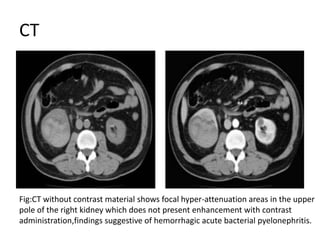

CT

Fig:CT without contrast material shows focal hyper-attenuation areas in the upper

pole of the right kidney which does not present enhancement with contrast

administration,findings suggestive of hemorrhagic acute bacterial pyelonephritis.